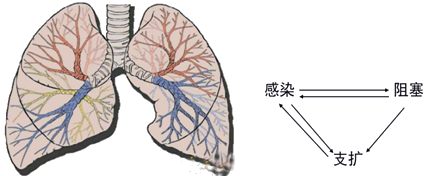

支气管扩张大多继发于急、慢性呼吸道感染和支气管阻塞。

支气管肺感染和阻塞是主要发病因素的疾病是

『答案解析』支气管扩张大多继发于急、慢性呼吸道感染和支气管阻塞。